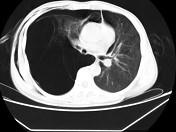

问题 男,32岁,被车撞伤后1小时,请结合影像图像选择其最可能的诊断为 ( )

选项 A.右侧气胸 B.右肺不张 C.右侧气胸并皮下纵隔气肿 D.右侧肺大疱并皮下纵隔气肿 E.支气管断裂

答案 C